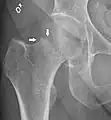

A case demonstrating a possible order of imaging in initially subtle findings:

Fracture (black arrow, pertrochanteric) versus a skin fold (white arrow).

X-rays of the affected hip usually make the diagnosis obvious; AP (anteroposterior) and lateral views should be obtained.